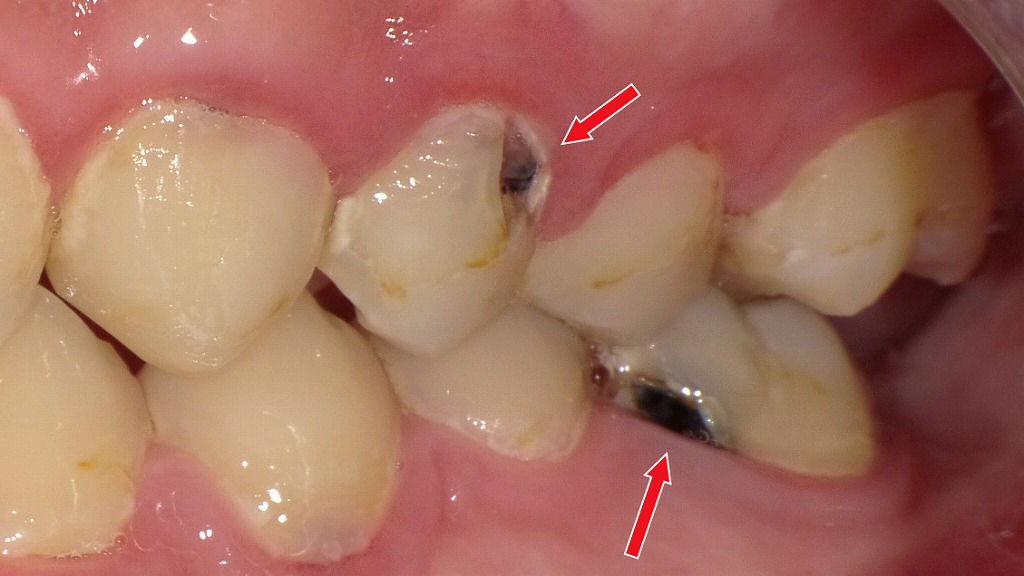

C2の場合:必要最小限の虫歯除去+CR充填

C2は虫歯がエナメル質を越えて象牙質まで進行した段階で、痛みやしみる症状が出始めることがあります。象牙質は軟らかく、C1より進行が早いため、自然な再石灰化での改善は困難です。

そのため、C2では虫歯に侵された部分のみをできる限り小さく削り、その後コンポジットレジン(CR)で修復する治療が基本となります。

早期にC2を治療することで、C3(神経に達する虫歯)への進行を防ぎ、最小限の介入で歯の寿命を守ることにつながります。